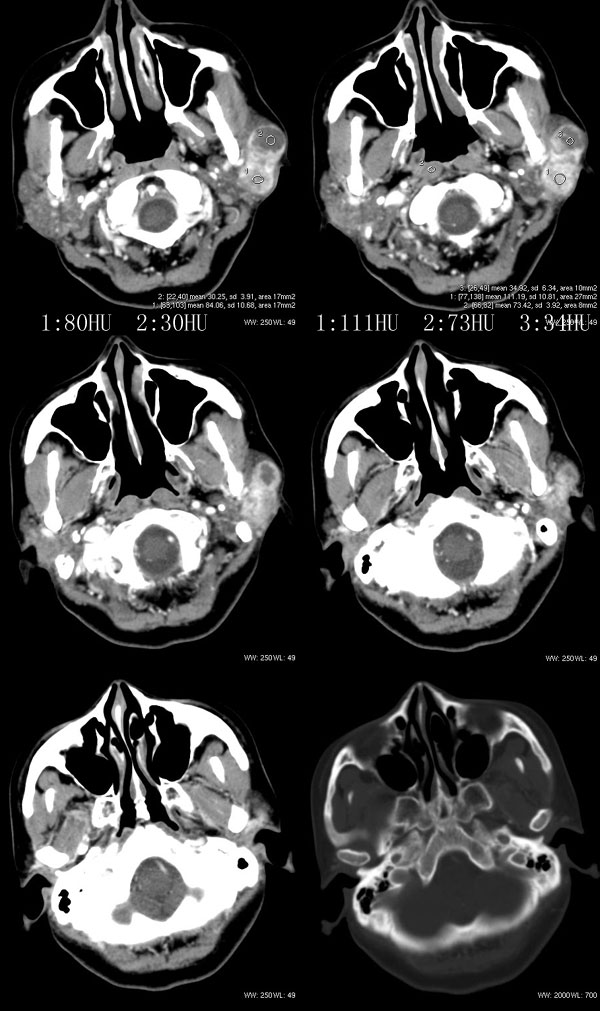

女性,43岁。左腮部肿物5年。体检:(肿物)质中,约5x4x4cm,边界清,固定。

左腮腺肿物,内可见低密度坏死区,增强扫描示肿块明显强化,且呈持续延迟强化,常规考虑腮混合瘤可能性大,但强化表现不太符合,不除外腮腺纤维血管瘤、神经鞘瘤、淋巴瘤及巨淋巴结增生症

强化方式符合:腮腺纤维血管瘤可能性大。另不除外:神经鞘瘤或淋巴瘤!

考虑左侧腮腺混合瘤。  肿瘤较大,边清,囊变,强化明显,皮肤及淋巴结无异示

左侧腮腺多形性腺瘤可能性大。1、是混合瘤中最常见的良性肿瘤;2、中年女性多见并且时间长症状轻;3、病灶内有低密度坏死区,增强时强化;4、其内有钙化,囊性部分未强化;5、需与囊性淋巴瘤相鉴别。